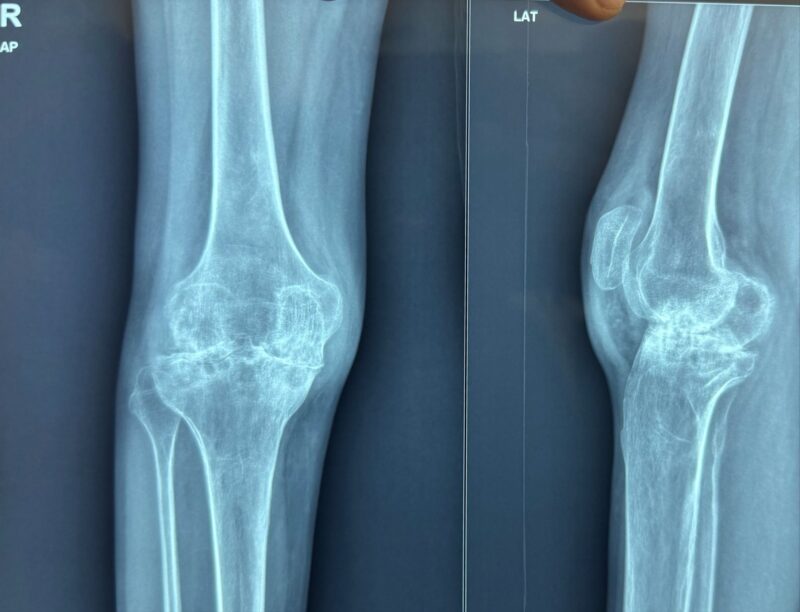

”Hemophilia Is a disease which cause joint damage in early age causing severe arthropathic changes in joints.

Hemophilia Arthropathy is a condition which causes disability in rather young age.

Recently, We did a TKA in a case of severe arthritis in a Hemophilia patient , giving him freedom to work like a normal human with pain free mobility.